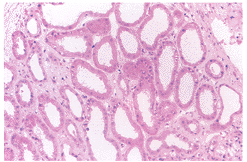

2.腎臟瘢痕 腎臟瘢痕(renal scarring)是一種局灶或彌散性不可逆的腎實質損害,腎瘢痕的形成與腎乳頭解剖形態特點有關,腎內反流常發生在腎上、下極的複合型乳頭乳頭管開口較大,乳頭較寬平當承受高的壓力易發生反流,反流時的逆流壓力顯著增高,膀胱充盈期的平均壓力3.07~3.60kPa,反流時膀胱收縮排尿期的壓力可增高至10.7kPa以上,壓迫腎組織形成瘢痕。新生兒及幼兒期腎組織發育未健全輕度反流也可形成瘢痕,輕度反流腎瘢痕的發生率為20%~35%重度反流可高達79%,腎臟瘢痕多在5歲以前發生,腎瘢痕亦可發生腎盂腎炎感染後而無反流存在,腎瘢痕持續至成人,其病理終發展至腎小球周纖維增生腎小球硬化和腎萎縮。根據腎形態學改變腎瘢痕可分為4期:

Ⅰ期:在腎上或下極僅見1處瘢痕。

Ⅱ期:超過2個以上瘢痕。

Ⅲ期:瘢痕擴大,腎萎縮。

Ⅳ期:固腎、小腎

分期有利於病情和預後的判斷。